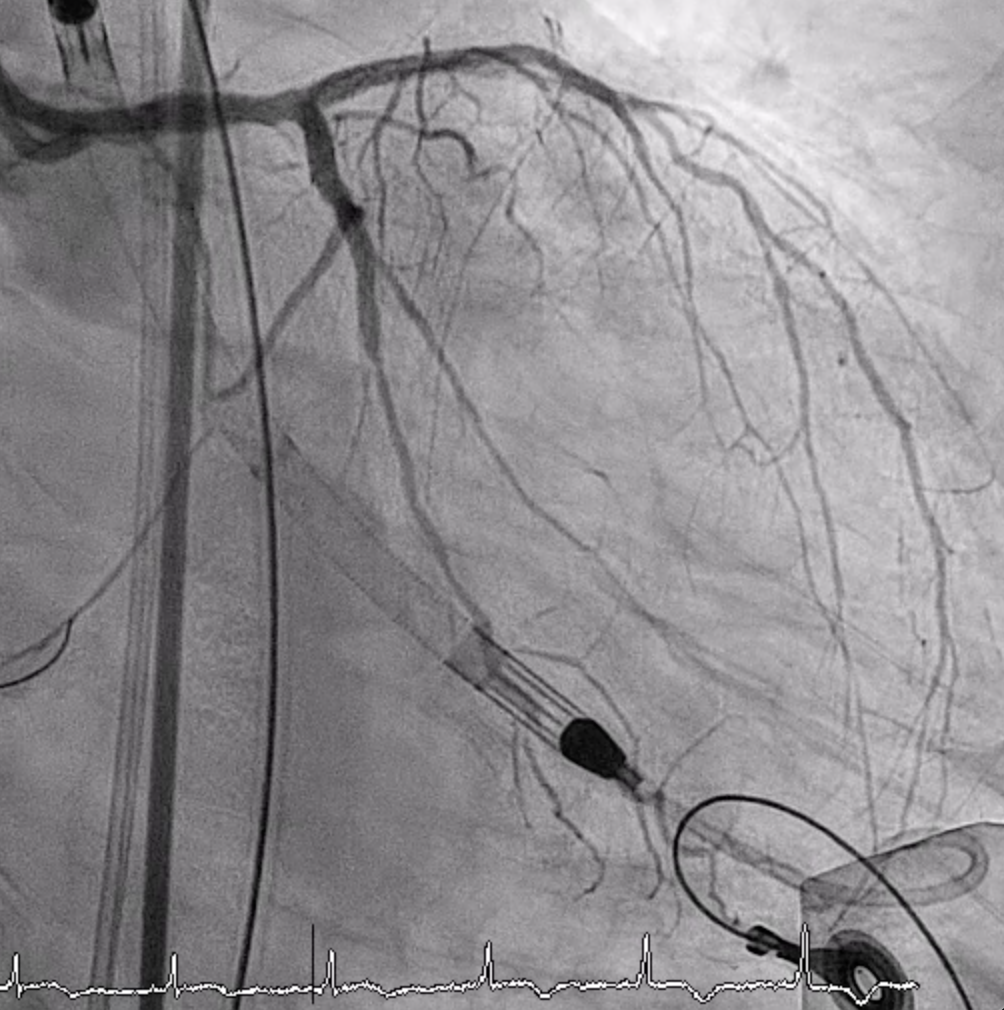

LMCA was engaged with an EBU 3.5. Several wires failed to cross the p-LAD CTO, but Gaia 1st entered the true lumen and advanced to DB2 via Finecross. Small-balloon predilation (1.2–2.0 mm) was done. IVUS confirmed true lumen and MLA 2.43 mm©÷ at the CTO entry. A double-catheter Sasuke technique enabled CTO crossing. A 2.0¡¿38 mm X-Skypoint stent was deployed, followed by POT and high-pressure post-dilation, achieving TIMI 3 flow.LCX Intervention: